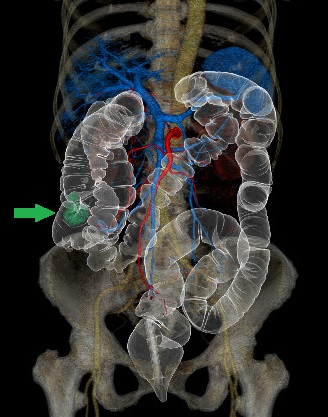

CTコロノグラフィー:上行結腸癌術前検査

当院は大腸CT検査技術施設認定を取得しています